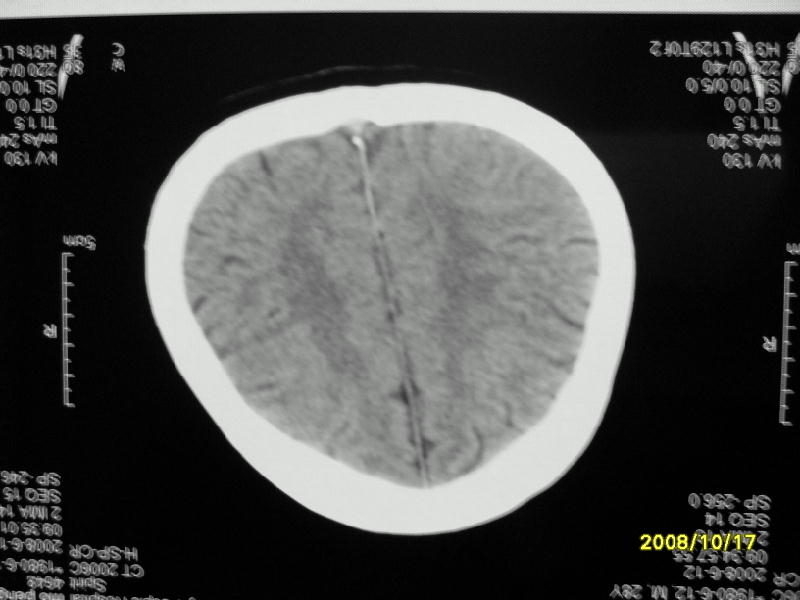

检查名称:     ct颅脑平扫           男     28岁

表现:左顶叶见斑点状致密影。边缘清,大小约0。3*1。0cm,余脑实质密度及灰白质结构示见异常。脑室系统大小,形态,密度未见异常。脑沟。脑裂。脑池未见异常密度影。中线结构无移位。

印象:左顶叶少许钙化灶

左顶叶见斑点状致密影。边缘清,大小约0。3*1。0cm,余脑实质密度及灰白质结构示见异常。脑室系统大小,形态,密度未见异常。脑沟。脑裂。脑池未见异常密度影。中线结构无移位。

印象:左顶叶少许钙化灶。